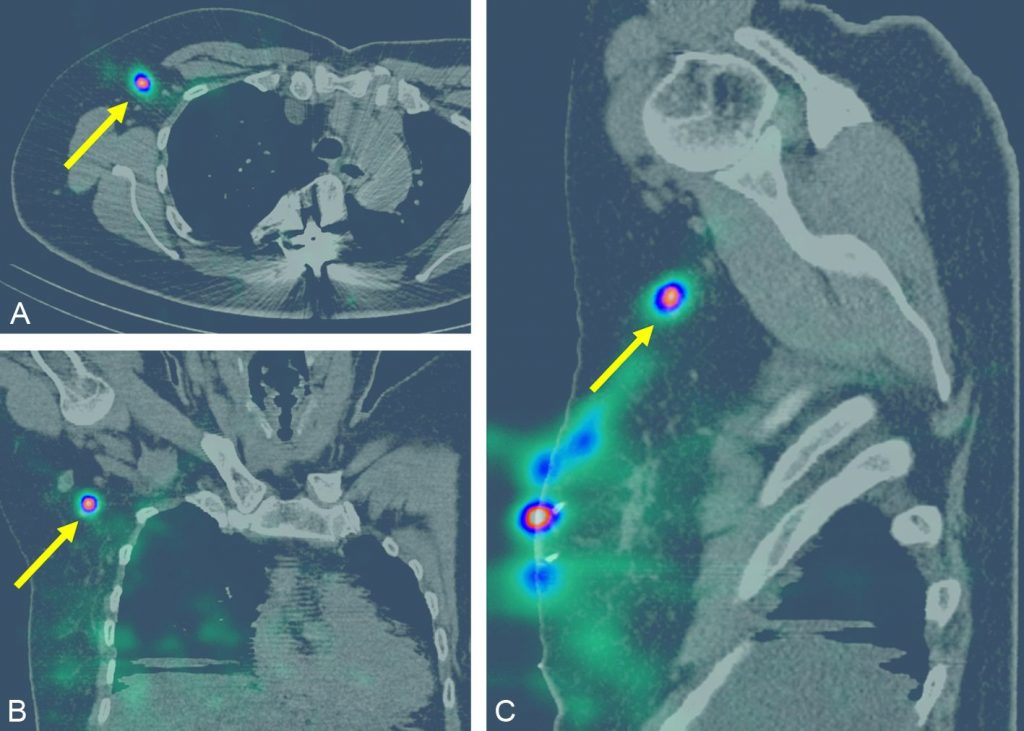

La lymphoscintigraphie aux colloïdes technétiés en préopératoire, pour la recherche de nœuds lymphatiques (« ganglions sentinelles »), est indiquée en routine pour les cancers du sein T1N0, T2N0 inférieur à 3 cm (jusqu’à moins de 5 cm après avis de la réunion de concertation pluridisciplinaire) si N0 clinique et/ou échographique et cytologie négative (stades I-IIA) (figure 34.4).

Fig. 34.4 Scintigraphie du ganglion sentinelle couplée à la TDM d’un cancer du quadrant supéro-externe du sein droit mettant en évidence un relais ganglionnaire hyperfixant en axillaire droit (flèches jaunes) sur les coupes transversales (A), coronales (B) et sagittales (C).

Source : CERF, CNEBMN, 2022.